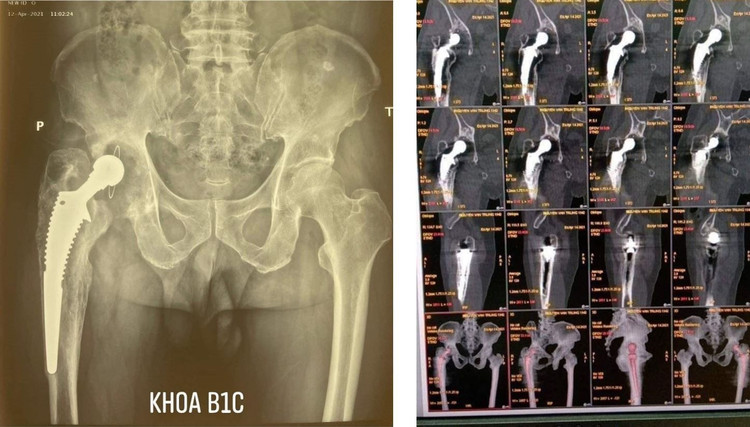

Các bác sĩ đã phải dùng loại khớp to đường kính 58mm và để chắc chắn với các đầu xương đã bị xi măng ăn rỗng, kíp phẫu thuật đã phải dùng loại chuôi dài đóng từ cổ xương đùi đóng tụt xuống đầu gối... Không những thế còn phải xử lý phần mềm bị xơ cứng, co kéo để đưa chân bệnh trở về bình thường. Sau gần 3 tiếng phẫu thuật, ca mổ đã thành công.

Hình ảnh phim X-quang sau phẫu thuật với ổ cối nhân tạo đủ lớn, đúng vị trí giải phẫu, chuôi khớp cố định suốt chiều dài dọc thân xương đùi.